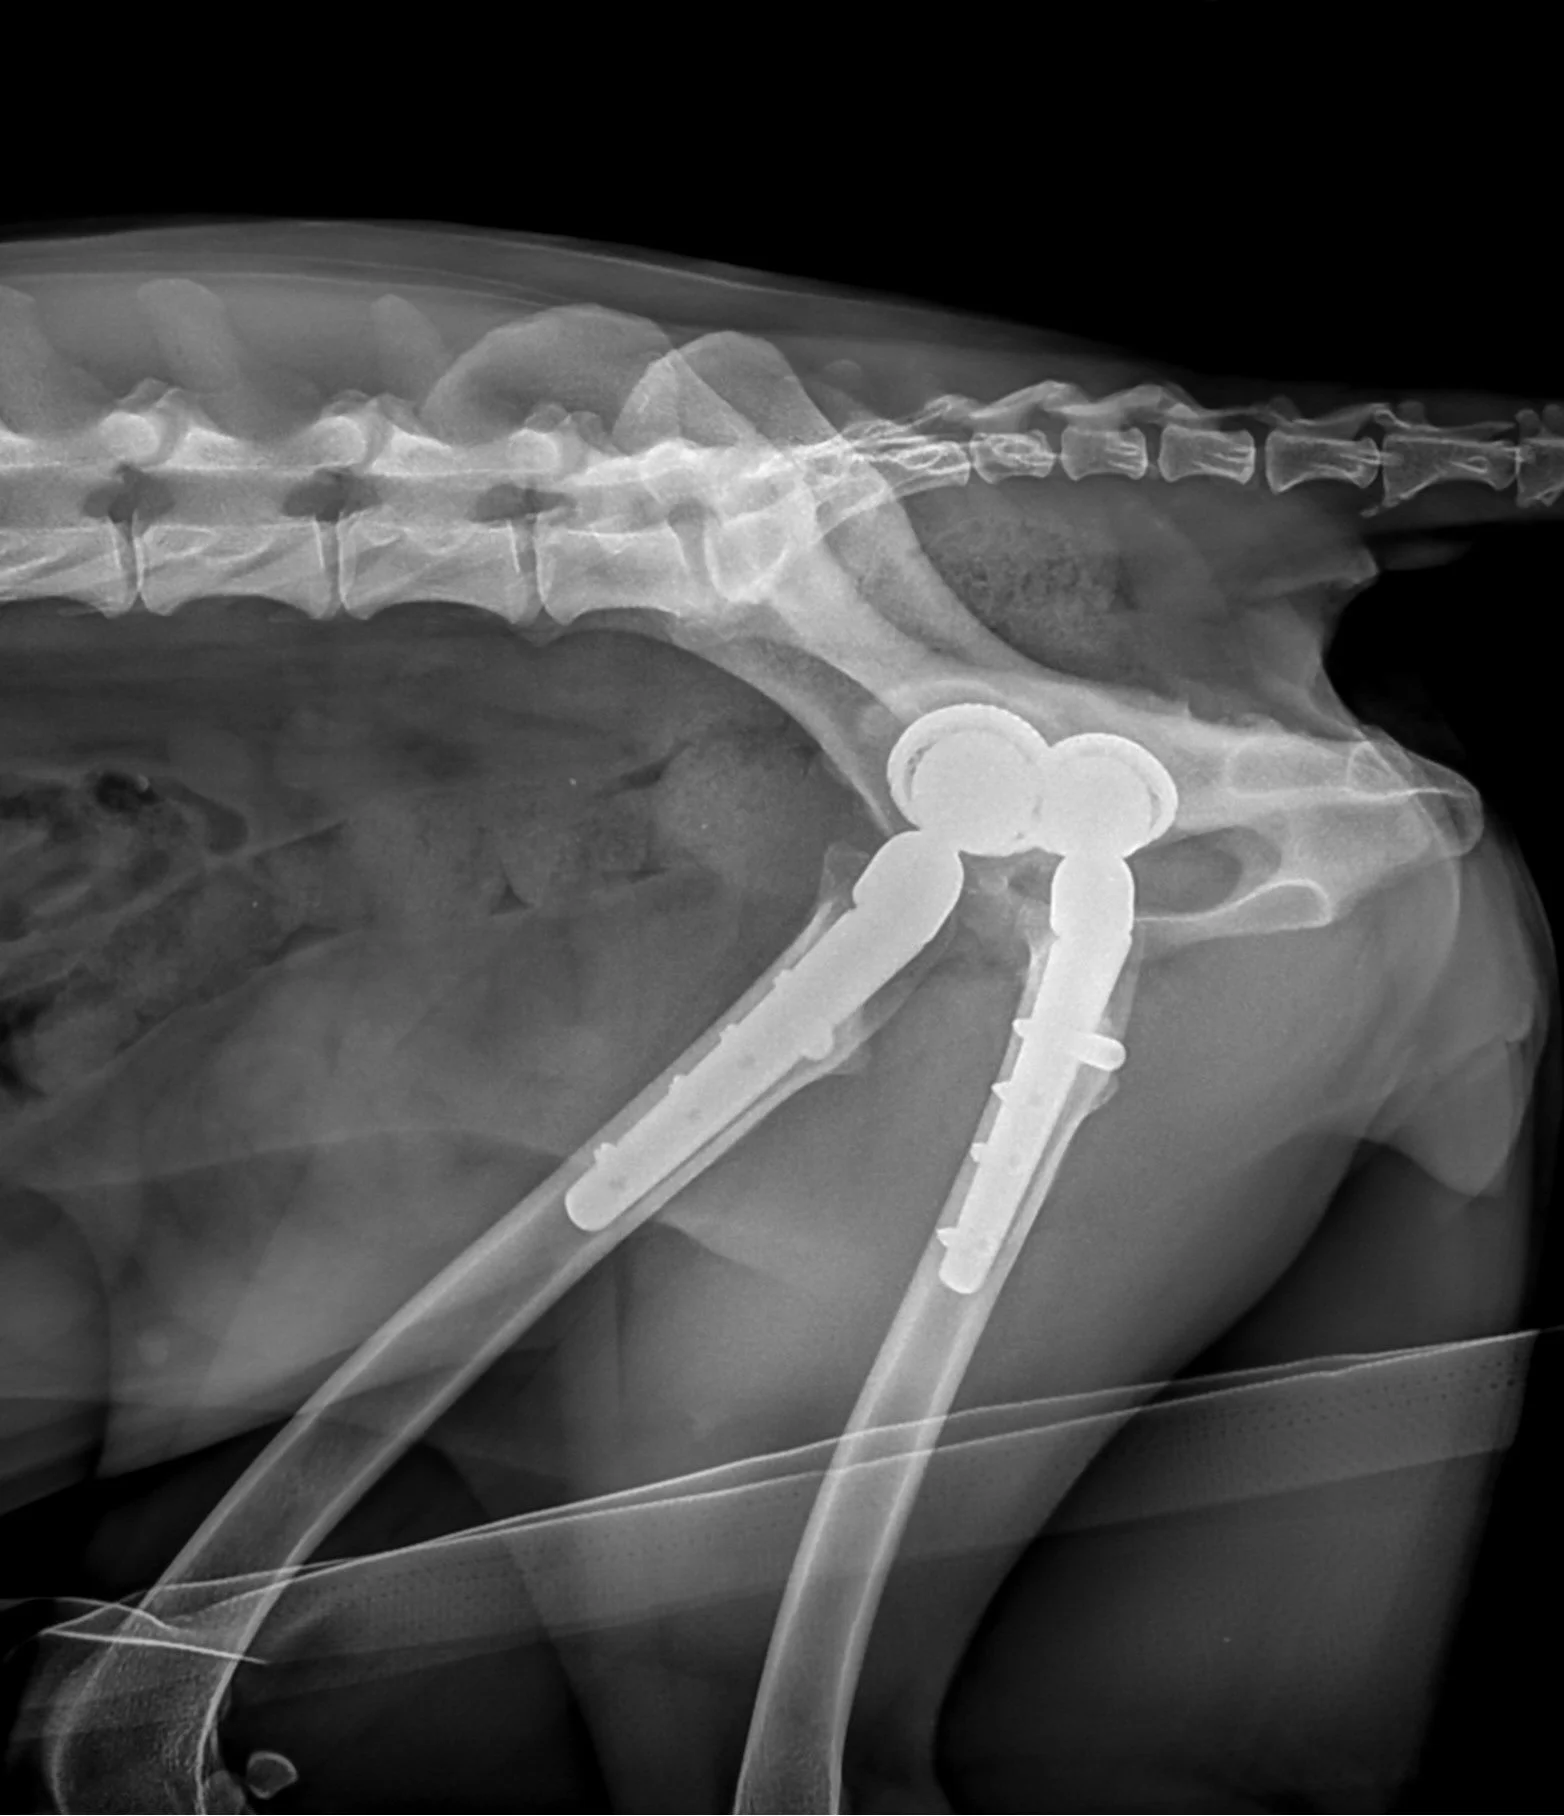

X-ray image showing a pelvis with bilateral hip replacements and surgical hardware.